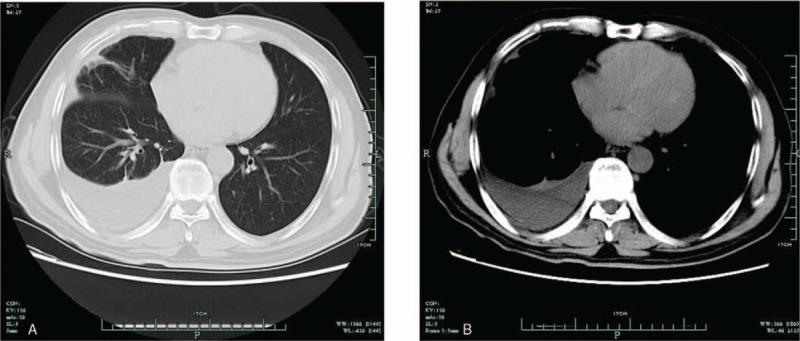

A 64-year-old man was hospitalized in our department and diagnosed as hepatic B cirrhosis. A computed tomography (CT) of the thorax showed a massive right pleural effusion without pulmonary parenchymal abnormalities. He was started on empirical treatment for pleural tuberculosis (TB). However, during his hospitalization, a right pleural effusion developed and fever was not controlled.

一名64岁男性因乙型肝炎肝硬化入住我科。胸部计算机断层扫描(CT)显示右侧大量胸腔积液,无肺实质异常。他开始接受结核性胸膜炎的经验性治疗。然而,住院期间,右侧胸腔积液仍持续存在,发热也未得到控制。